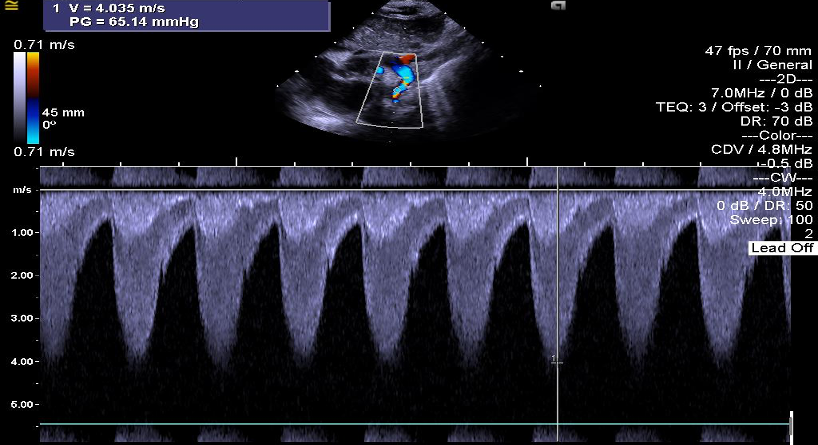

Giunge alla nostra attenzione una bambina nata da poche ore in un ospedale periferico, da cui è stata trasferita per soffio sistolico, ipoperfusione cutanea, polsi femorali deboli. Posta la diagnosi clinica ed ecocardiografica (Figura) di coartazione aortica serrata, è stata iniziata terapia ev con prostaglandina E1 (PGE1) e la piccola è stata avviata a intervento cardio-chirurgico di de-coartazione, eseguito in quinta giornata di vita.